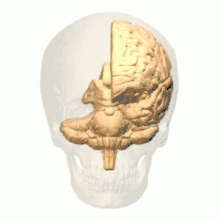

أسماء المناطق المبينة بالأرقام كما يلي:

1) القطب الجبهي ( Polus frontalis)

2) القطب القذالي ( Polus occipitalis )

3) الشق الطولاني للمخ ( Fissura longitudinalis cerebri)

4) التلفيف الجبهي العلوي ( Gyrus frontalis superior)

5) التلفيف الجبهي الوسطي ( Gyrus frontalis medius)

6) التلفيف الجبهي السفلي ( Gyrus frontalis inferior)

7) الثلم الجبهي العلوي ( Sulcus frontalis superior)

8) الثلم الجبهي السفلي ( Sulcus frontalis inferior)

9) الثلم أمام المركزي ( Sulcus praecentralis)

10) التلم المركزي ( Sulcus centralis)

11) الثلم خلف المركزي ( Sulcus postcentralis)

12) الثلم داخل الفص الجداري ( Sulcus intraparietalis)

13) الثلم الوحشي (شق سلفيوس) ( Sulcus lateralis (Fissura Sylvii))

14) التلفيف أمام المركزي ( Gyrus praecentralis)

15) التلفيف خلف المركزي ( Gyrus postcentralis)

16) الفصيص الجداري العلوي ( Lobulus parietalis superior)

17) الفصيص الجداري السفلي ( Lobulus parietalis inferior)

18) الفص القذالي ( Lobus occipitalis)

19) التلفيف الصدغي العلوي ( Gyrus temporalis superior)

20) التلفيف فوق الهامشي (؟) ( Gyrus supramarginalis)

الفص الجبهي (Frontal lobe)

الفص الصدغي (Temporal lobe)

الفص الجداري (Parietal lobe)

الفص القذالي (Occipital lobe)

الفص الحوفي (Limbic lobe)

الجَزيرَة (Insula)